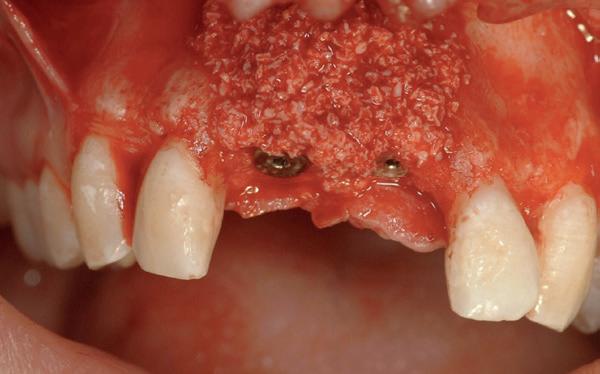

In het onderfront werd autoloog bot geoogst uit de kin regio ten behoeve van augmentatie (afbeelding

9. Botopbouw onderfront

9). In de bovenkaak werd bilateraal een sinuslift uitgevoerd. Aansluitend werden in beide kaakhelften implantaten geplaatst (afbeelding 10).